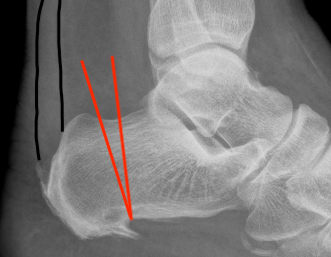

Pavlov's parallel pitch lines

- lateral weight bearing x-ray

- draw parallel pitch lines

- defines Haglund's deformity to be removed (above second line)

Fowler's angle - Normal < 70° / Abnormal > 80°